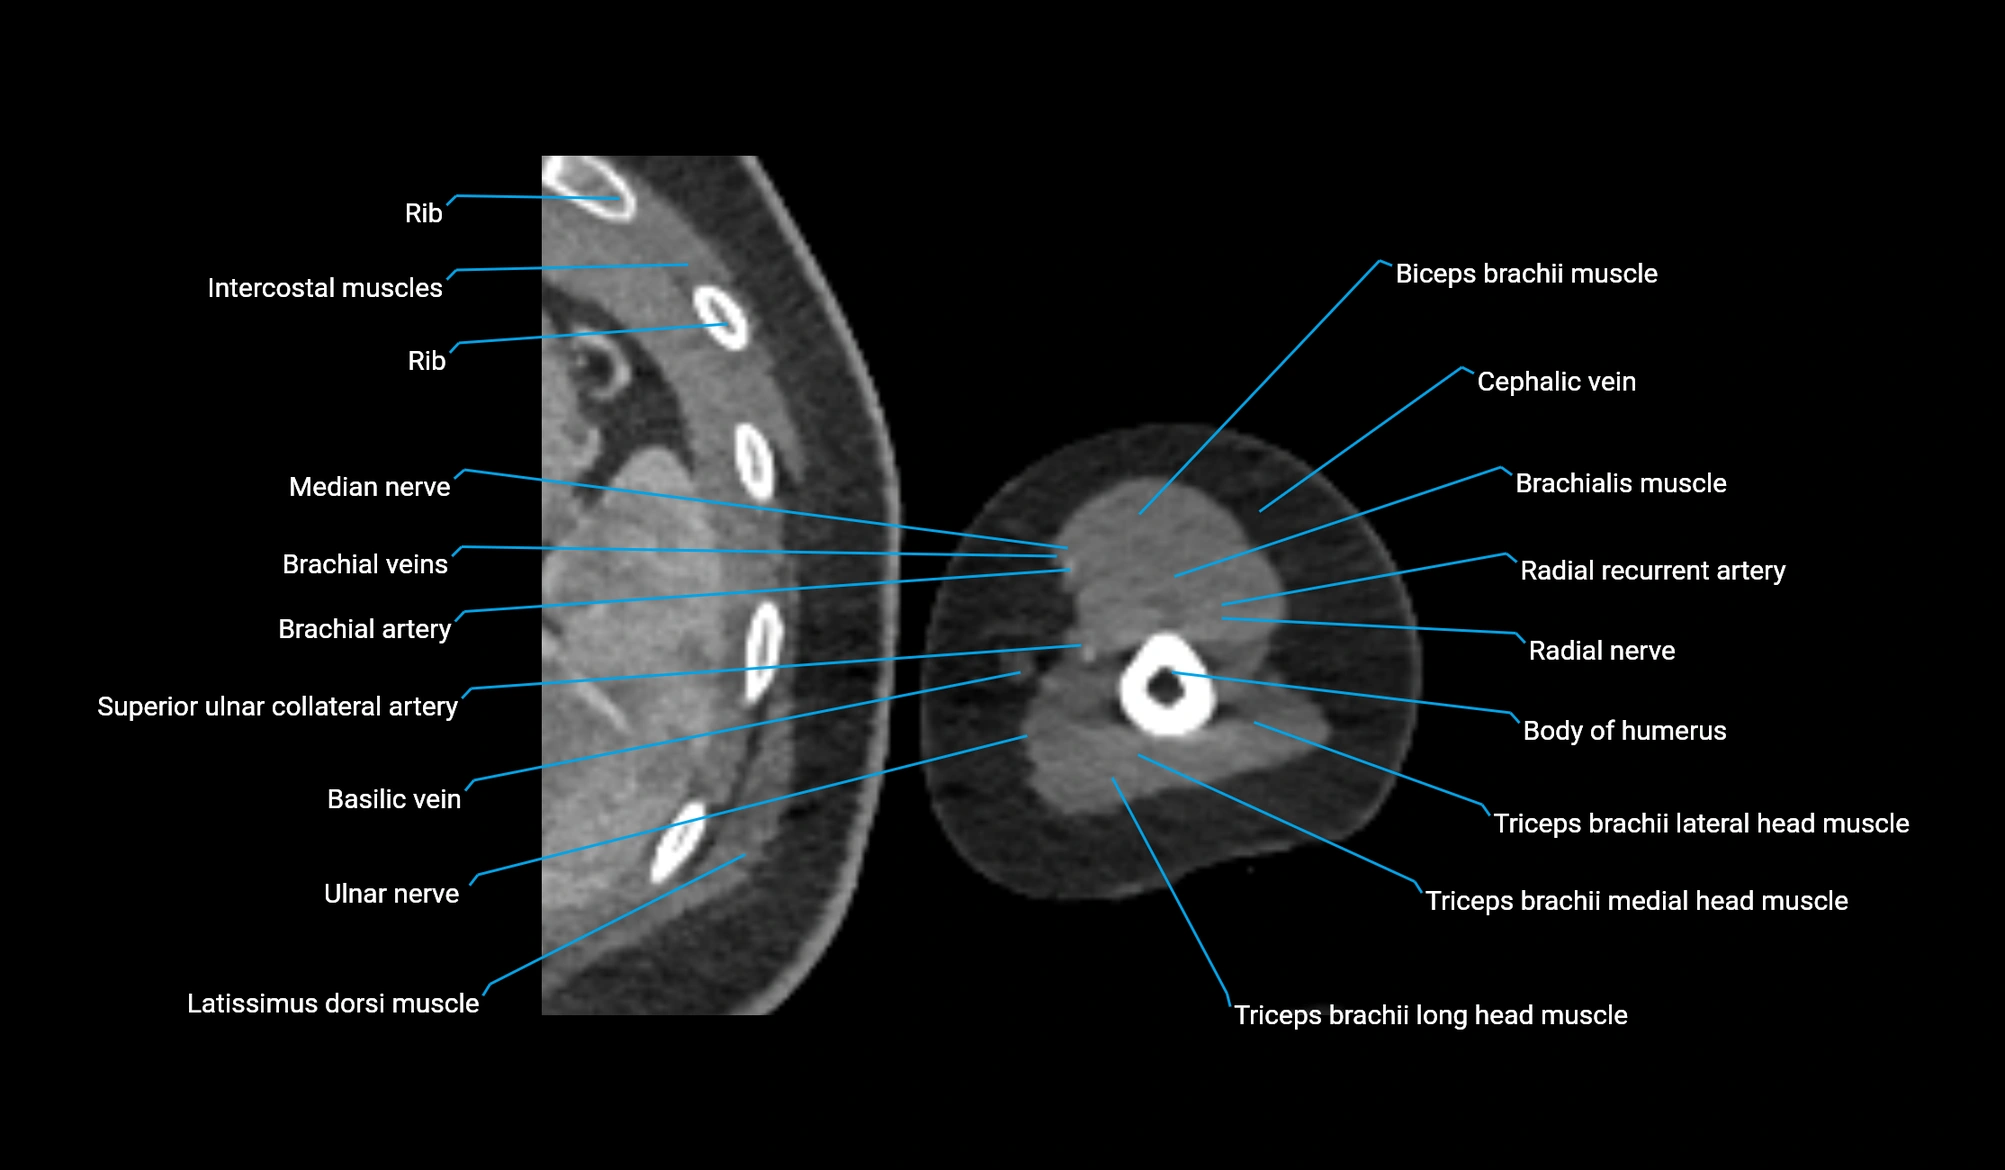

- Body of humerus

- Brachial artery

- Brachialis muscle

- Brachioradialis muscle

- Cephalic vein

- Long head of triceps brachii muscle

- Lateral head of triceps brachii muscle

- Medial head of triceps brachii muscle

- Median nerve

- Radial nerve

- Radial recurrent artery

- Superior ulnar collateral artery

- Ulnar nerve